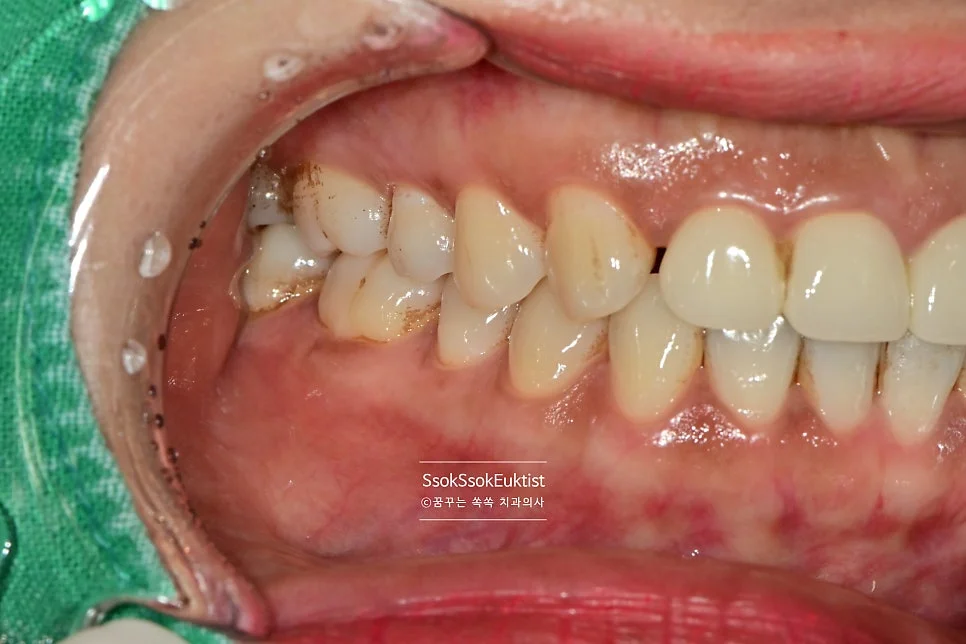

수면 스케일링 전후 비교 구강 사진

수면 스케일링 전후 비교

스케일링 전 구강 정면 임상 사진

구강 정면 — 관리가 조금 필요해 보이지만…

이 증례에서도 사진을 보면 구강 내 관리가 조금 필요해 보입니다만,

스케일링 전 치석 착색 상태

Before — 스케일링 전